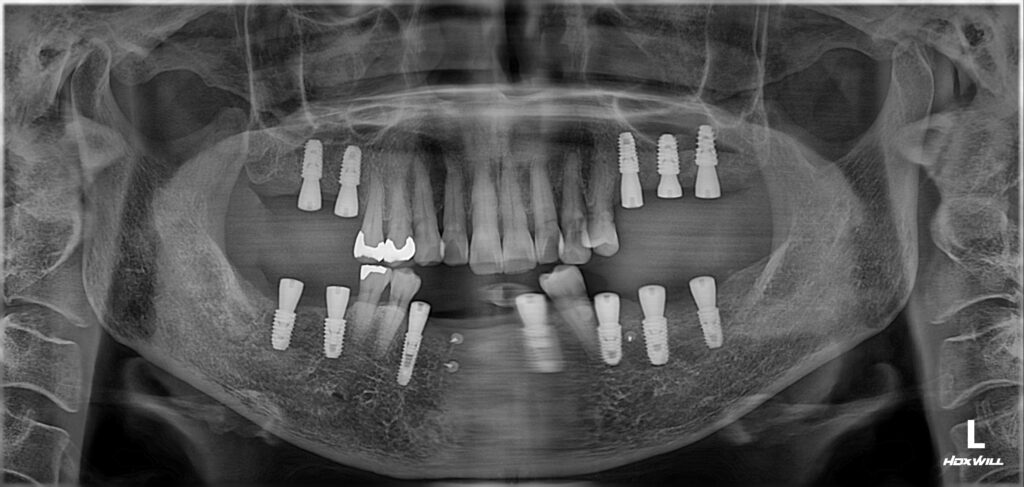

보다 정확한 수술을 위해 내비게이션 임플란트 시스템을 사용하였습니다.

잇몸뼈가 많이 무너진 부위에는 뼈이식을 함께 시행했고, 아래와 같이 수술이 완료되었네요.

수술 후 약 3개월간 골 유착(뼈와 임플란트가 붙는 과정) 기간을 기다렸습니다.

그 후 특수 장비를 이용해 골 유착 정도를 측정한 결과, 모든 부위에서 안정적인 수치가 확인되었습니다.